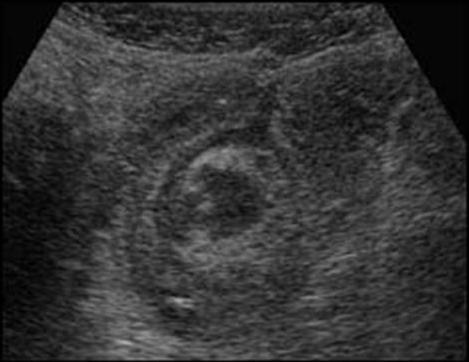

Echographie

transcutanee : Technique de tres utilise pour verifele

canal de l'anus et la cul de sac inferieure gazeuse du colon

Aspect ecographique une abces entre deux anses du

grele dans une maladie de Crohn . En haute de

frequence on peut voyait image de epaissisement de

la paroi du colon ou ileon terminale . |